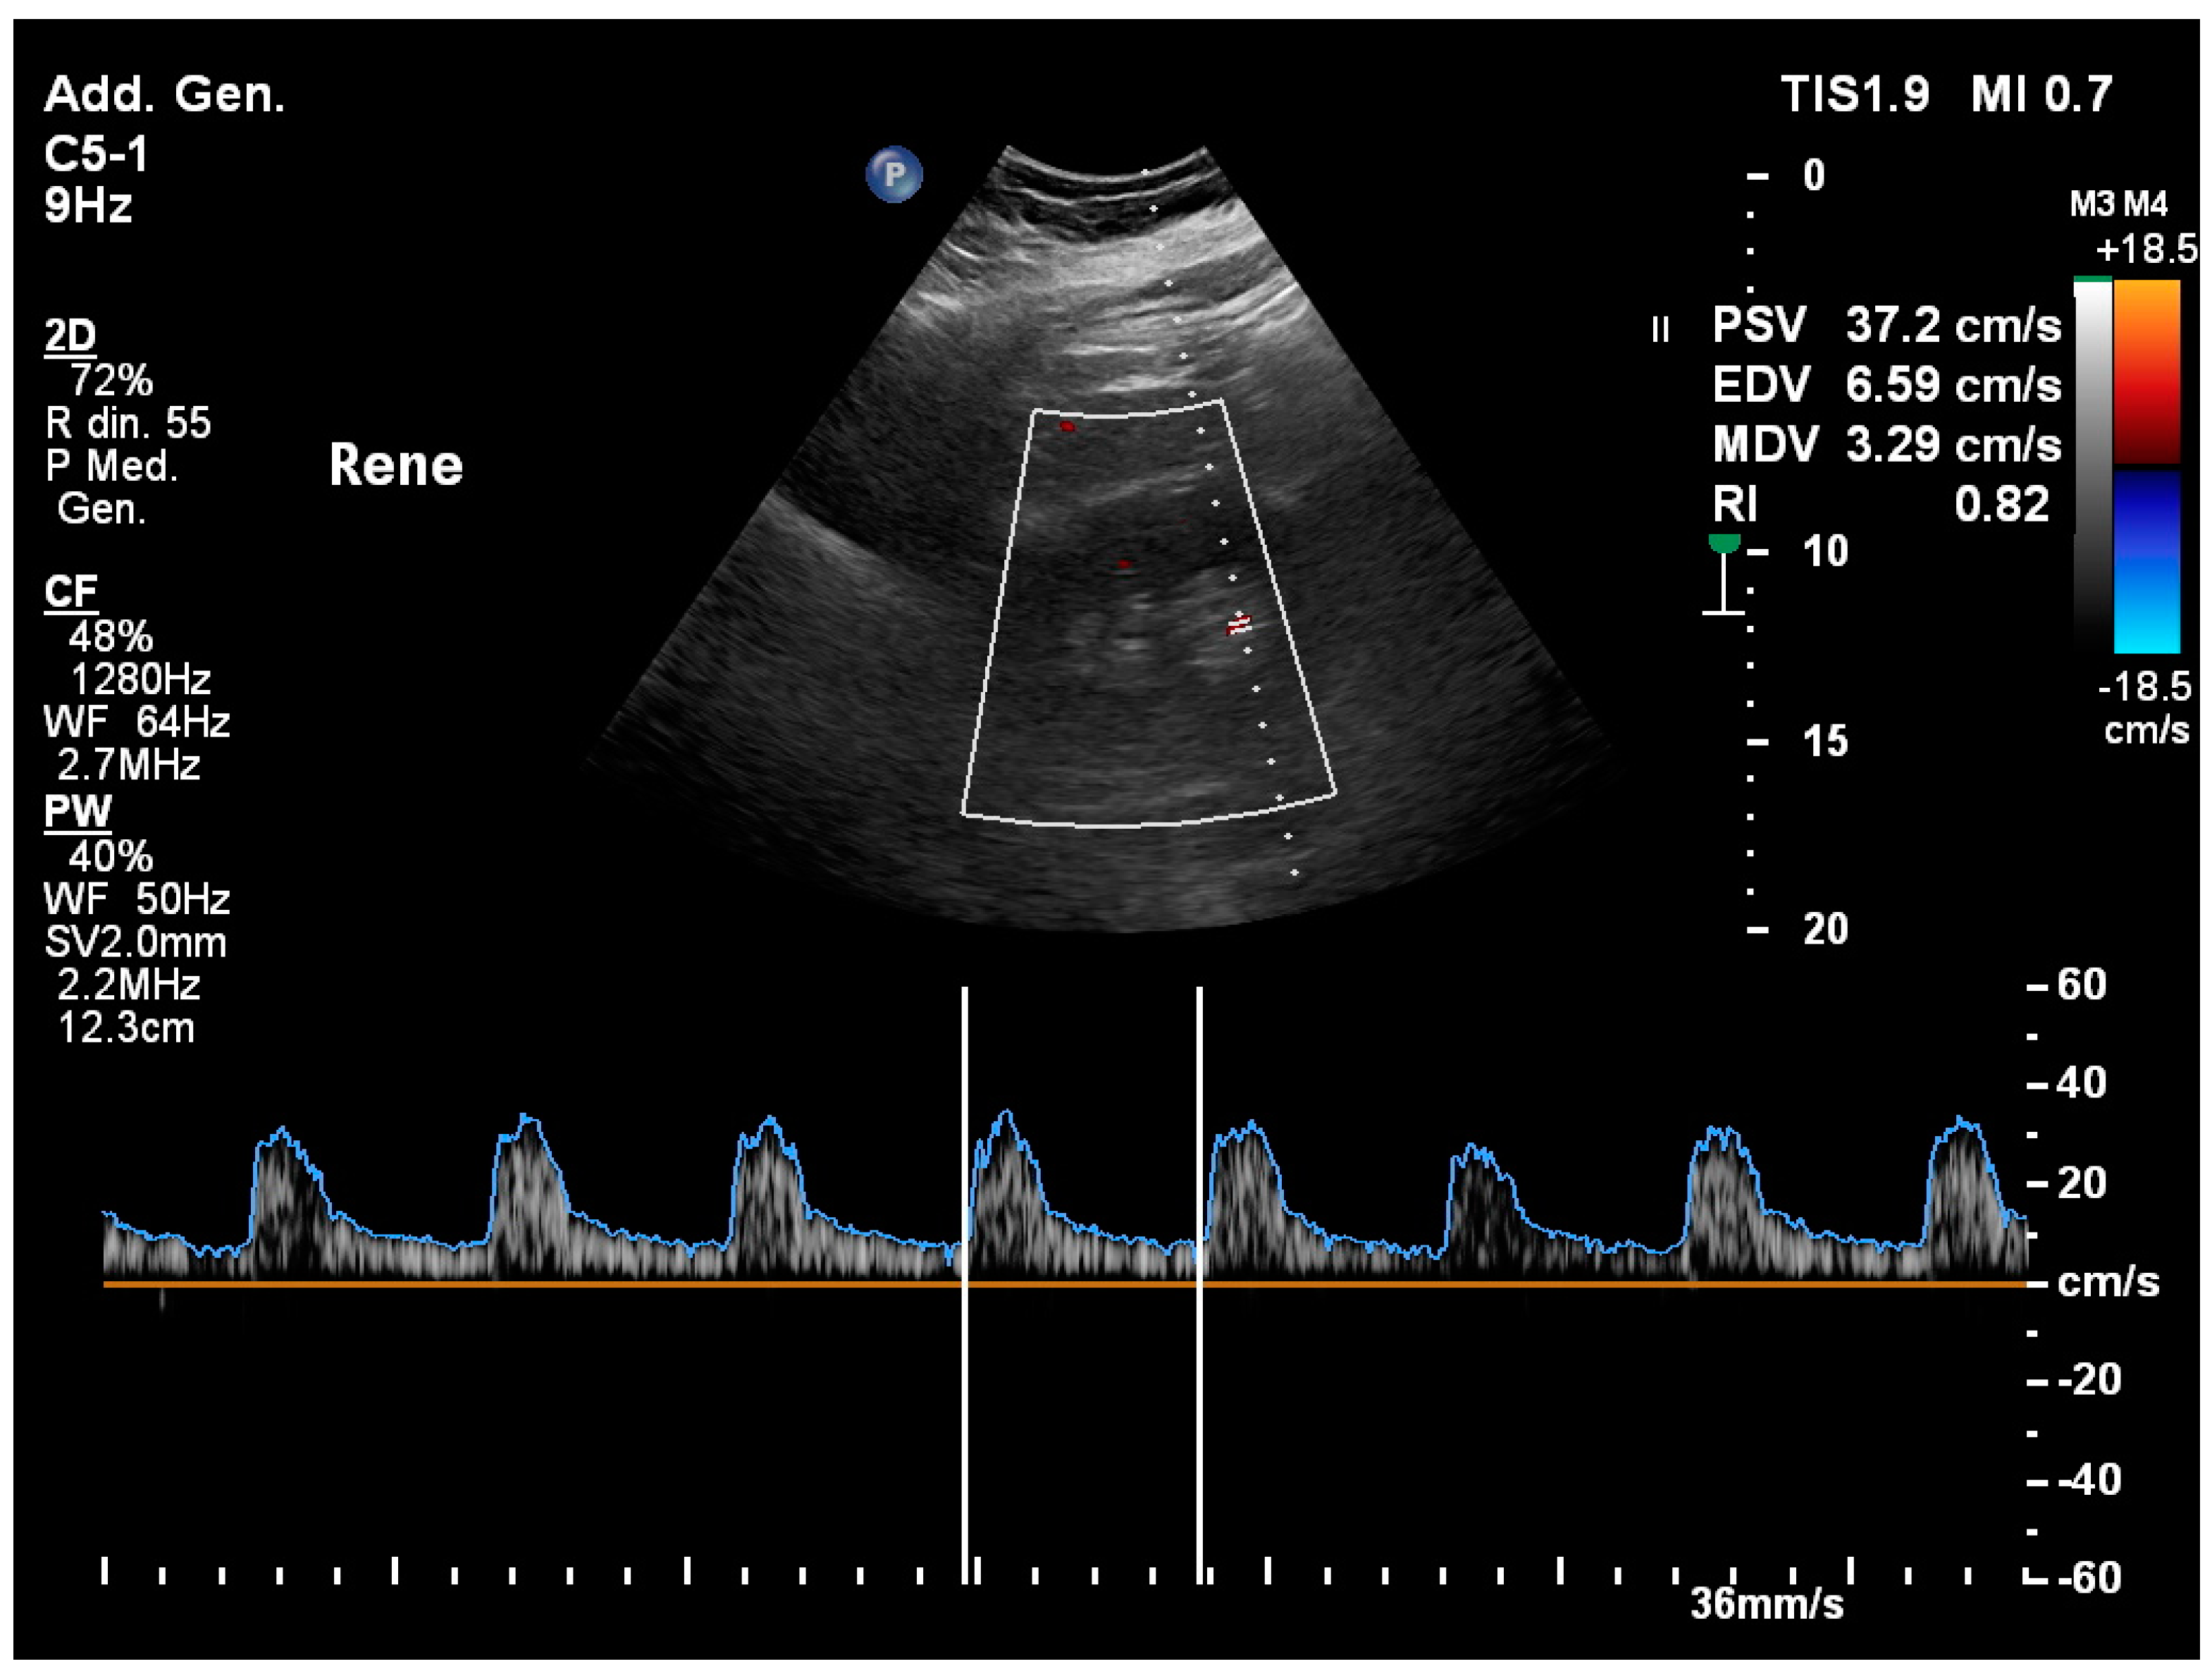

3.13. Renal Resistivity Index